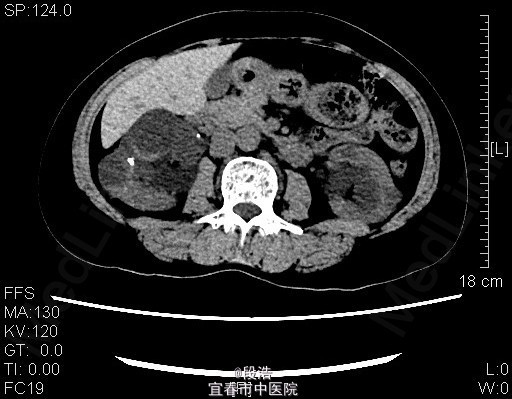

1、中年女性,体检发现双侧肾囊肿2年 2、患者于2年余前至当地医院体检发现双侧肾囊肿,当时诉腰部稍酸胀,尿量稍增多,无尿频、尿急、尿痛,无排尿困难,无血尿、脓尿等。起病以来,患者一般情况尚可,体重无下降

3、查体:未见明显异常 4、辅助检查:2013-4-11我院中腹部CT结果考虑多囊肝(未给出图像),双侧多囊肾,双肾囊壁部分钙化;双肾多发结石。2015年5月复查结果同前。

5、诊断:多囊肝,双侧多囊肾,双肾多发结石 6、入院后完善相关检查,生化,心电图,胸片未见异常,复查ct提示多囊肝,双侧多囊肾,双肾囊壁部分钙化;双肾多发结石,排除手术禁忌症后,行腹腔镜下左肾囊肿去顶术,术后予“注射用头孢美唑钠(先锋美他醇)”抗感染、抑酸、静脉营养补液等处理,术后恢复良好,顺利出院。术后半年复查再决定另一侧的处理方式。